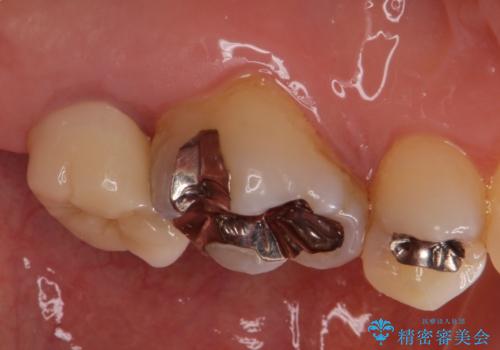

- 奥の銀歯を白くしたいとの事で来院。

痛みはないとの事でしたがレントゲンを撮影したところ根の先に病巣がある事がわかりました。

被せ物、古い材料を徹底的に除去し、ラバーダム防湿にて無菌的処置を行い、セラミックの被せ物で治療を行いました。